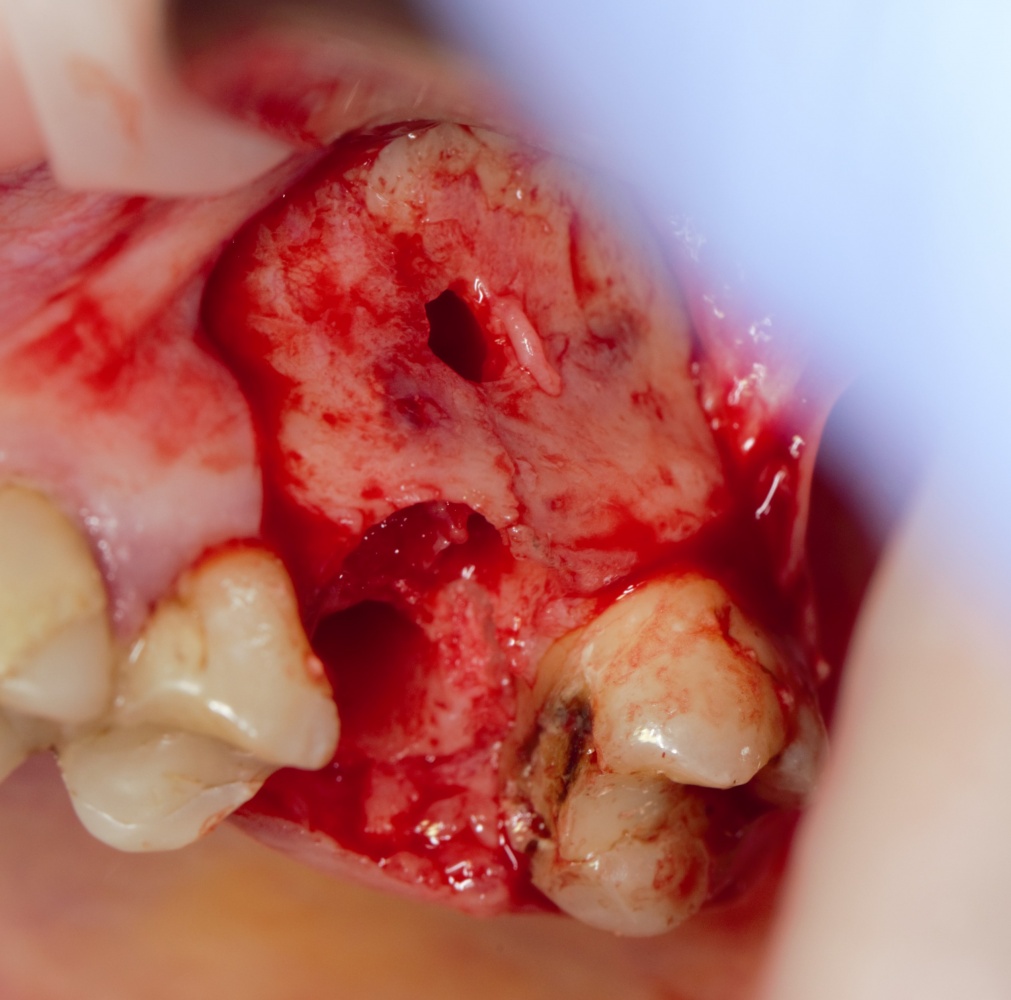

Простой синуслифтинг. Часть I.